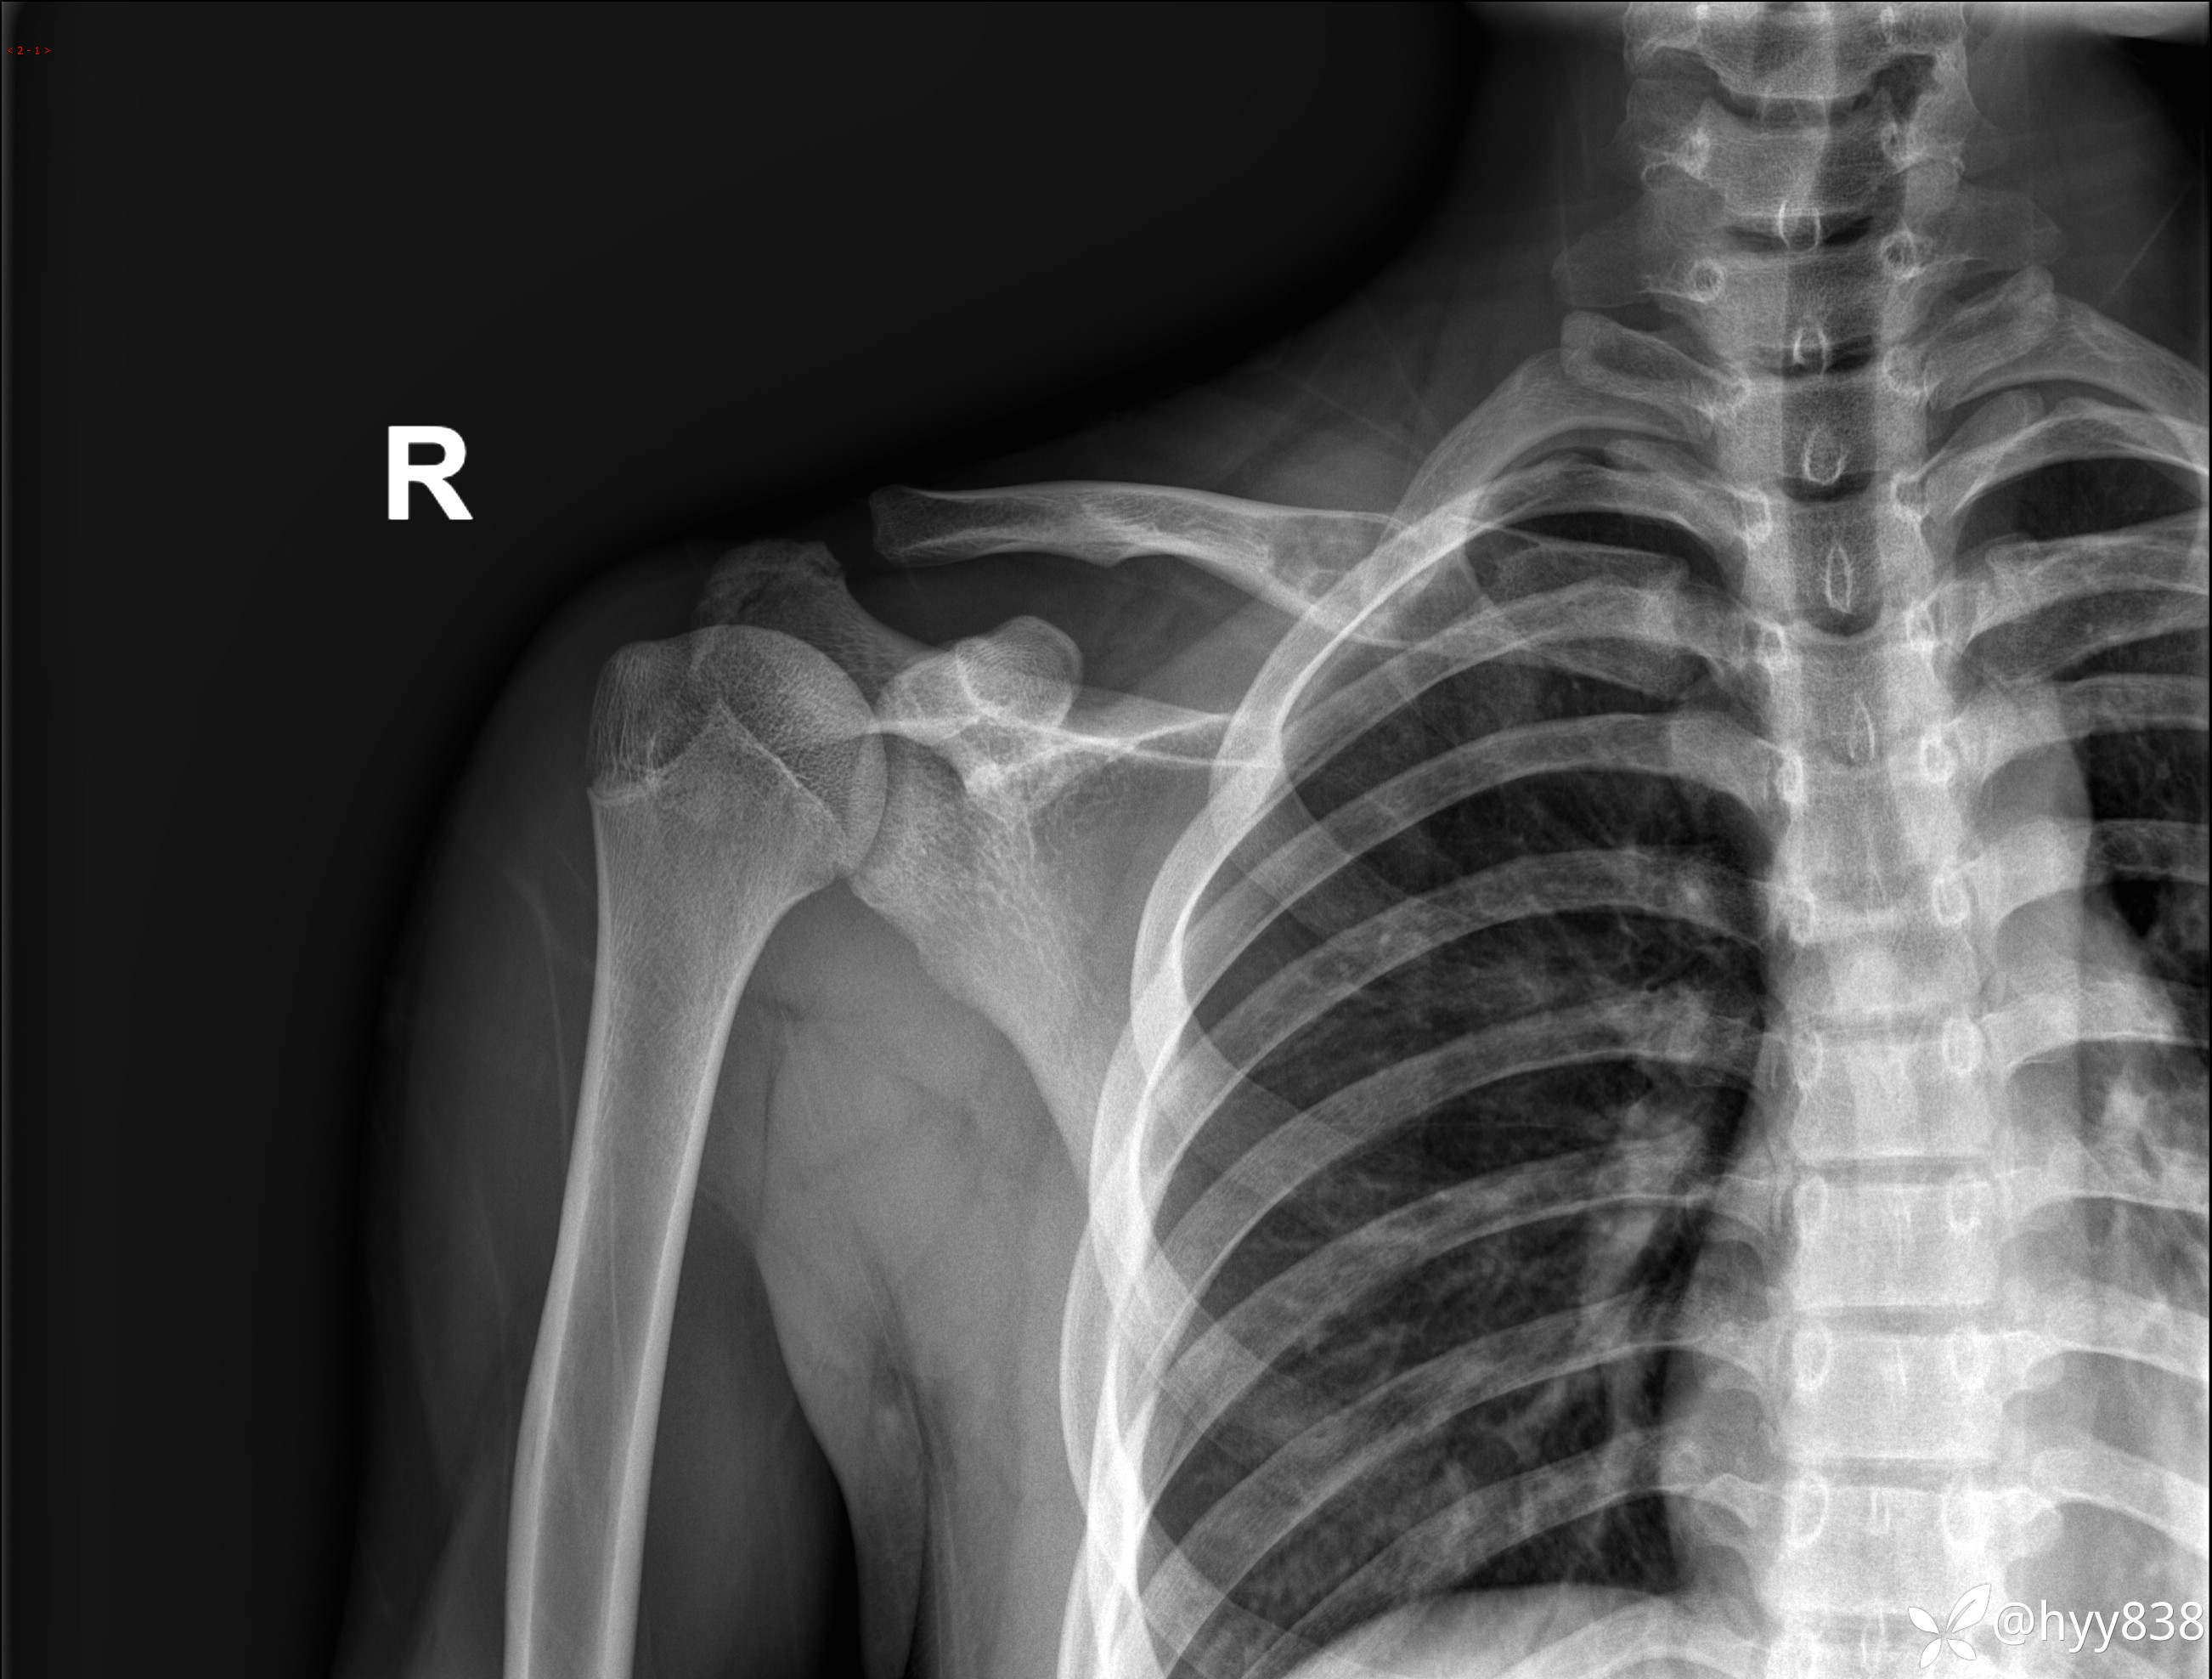

平片